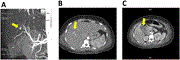

Simultaneous total robotic right hemicolectomy and right partial nephrectomy

Yohei Sanmoto and others

Journal of Surgical Case Reports, Volume 2023, Issue 7, July 2023, rjad434, https://doi.org/10.1093/jscr/rjad434